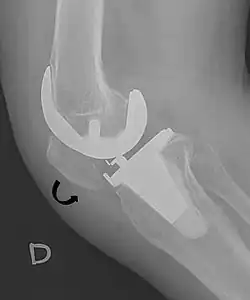

- ^ Melloni, Pietro; Veintemillas, Maite; Marin, Anna; Valls, Rafael (2013). "Imaging Patellar Complications After Knee Arthroplasty". Arthroplasty - Update. doi:10.5772/53666. ISBN 978-953-51-0995-2. (CC-BY-3.0)

- ^ a b Douglas Dennis (2017-02-25). "TKA in Patella Baja (Infera)". Orthobullets. Retrieved 2019-02-08.